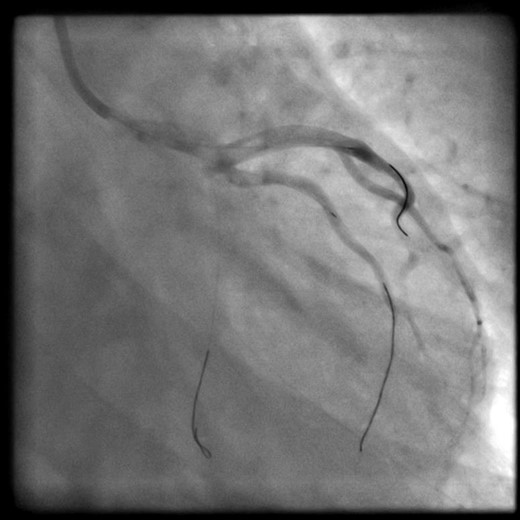

The patient acutely became hemodynamically unstable and suffered a cardiac arrest. Cardiopulmonary resuscitation was started and the patient was intubated. Return of spontaneous circulation (ROSC) was achieved with inotropes, vasopressors and intra-aortic balloon counterpulsation. Following ROSC, angiographic wires were passed into the coronaries. However, the operator was unable to wire the true lumen of the circumflex artery (Fig. 2).

Wires left into the coronaries during transfer. LAD and intermediate: true lumen successfully wired. Cx: unable to wire true lumen.